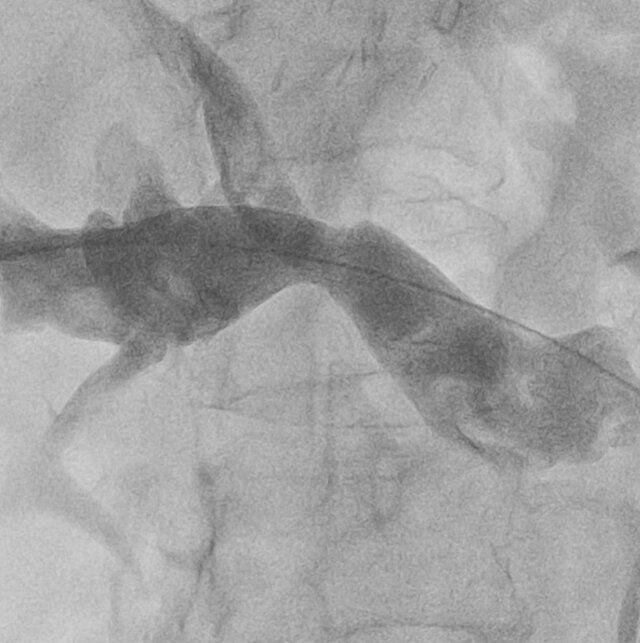

Results: All patients were treated using percutaneous transhepatic correction of portal vein stenosis with balloon plasty. In all cases ultrasound guided percutaneous approach to portal vein was performed. Balloon plasty was performed in all cases, no stents were used. No post operative complications occured. Signs of portal hypertension and graft dysfunction regressed after an average of one month of observation. There were no recurrences during 12 months of follow-up.